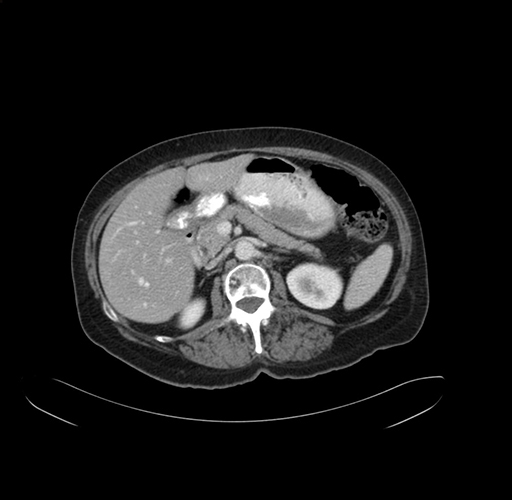

Pre-Chemo: Axial Venous